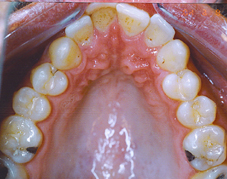

| תמונת שיניים עליונות לפני הטפול | מודל וירטואלי של השיניים העליונות לפני הטפול | |